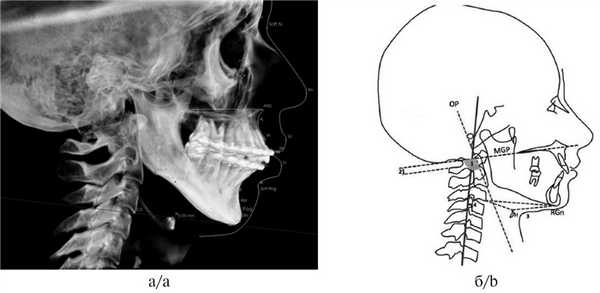

III. Анализ краниомандибулярных нарушений (необходим при планировании комплексного лечения совместно с миофункциональным терапевтом) и оценка объема дыхательных путей для исключения синдрома обструктивного апноэ. Оценка положения подъязычной кости (краниоцервикальный цефалометрический анализ по M. Rocabado) и языка. Измерение проводится следующим образом: необходимо провести линию от передненижнего угла тела III шейного позвонка к наиболее нижней точке подбородочного симфиза Me (Menton), далее к начерченной линии проводят перпендикуляр от наиболее передней и верхней точки подъязычной кости. В норме длина перпендикуляра должна составлять 5,0±2,0 мм (рис. 6).

Рис. 6. Подъязычный треугольник по M. Rocabado (а) и оценка положения подъязычной кости к основанию тела нижней челюсти (0,09 мм) (б).